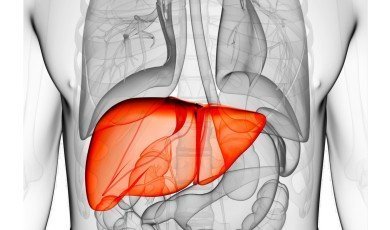

Pancreatic Diseases Overview

With the right treatment and lifestyle c...